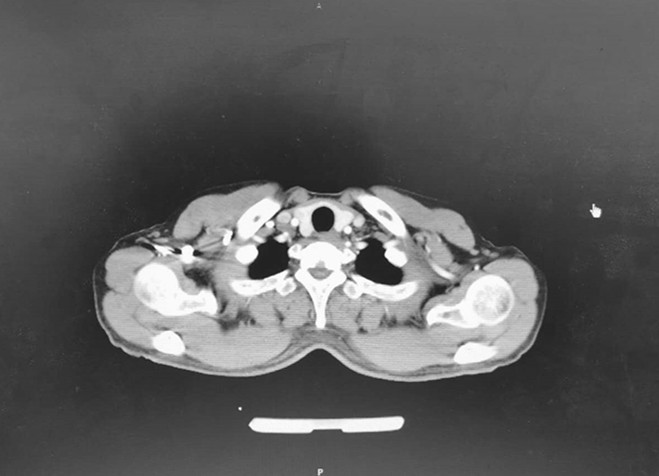

7月8日CT结果

2020年7月8日:疗效评价PR。